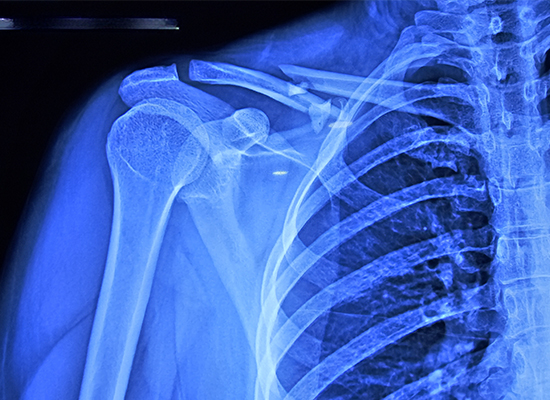

Пациентка, 34-летняя женщина, получила перелом правой ключицы, классифицированный как тип 1 по Оллману, то есть перелом средней части диафиза. Этот тип травмы часто может привести к осложнениям, если не лечить его правильно. Изучив состояние пациентки и проанализировав результаты визуализации, доктор Педро рекомендовал процедуру открытой репозиции и внутренней фиксации (ORIF) с использованием фиксирующей пластины S-ключицы.

У 34-летней пациентки был перелом средней части диафиза I типа по Оллману с множественными фрагментами.

Из-за многофрагментарности и смещения перелома консервативная фиксация не позволила добиться выравнивания, поэтому был выбран ORIF.